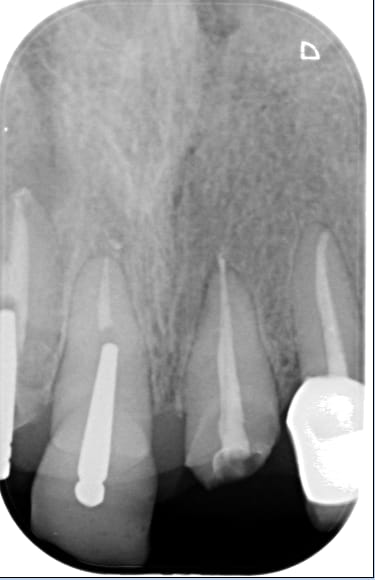

C'est une jeune femme qui a d'affreuses CCM faites il y a 8ans en surcontour gingival au niveau 12-11-21-22..

Ces CCM sont très volumineuses, débordant dans le sulcus avec une limite de préparation en congé hyperagressive et très sous gingivale... La patiente a un sourire gingival et on ne voit que cette gencive rouge violacée hypertrophiée..

J'ai déjà démonter 3 des 4 CCM, fait les traitements endo et j'ai posé les provisoires en retrait du congé pour aider à la cicatrisation ???

Le problème est qu'au bout de 2mois, je vois très peu d'amélioration de l'état gingival sur les 3 premières provisoires... Et mes provisoires sur 12, 11 et 21, en retrait du congé traumatique sont peu rétentives alors je m'inquiète pour les définitives en CCC..

T'as un cas galère, le rapport racine/couronne est flippant.